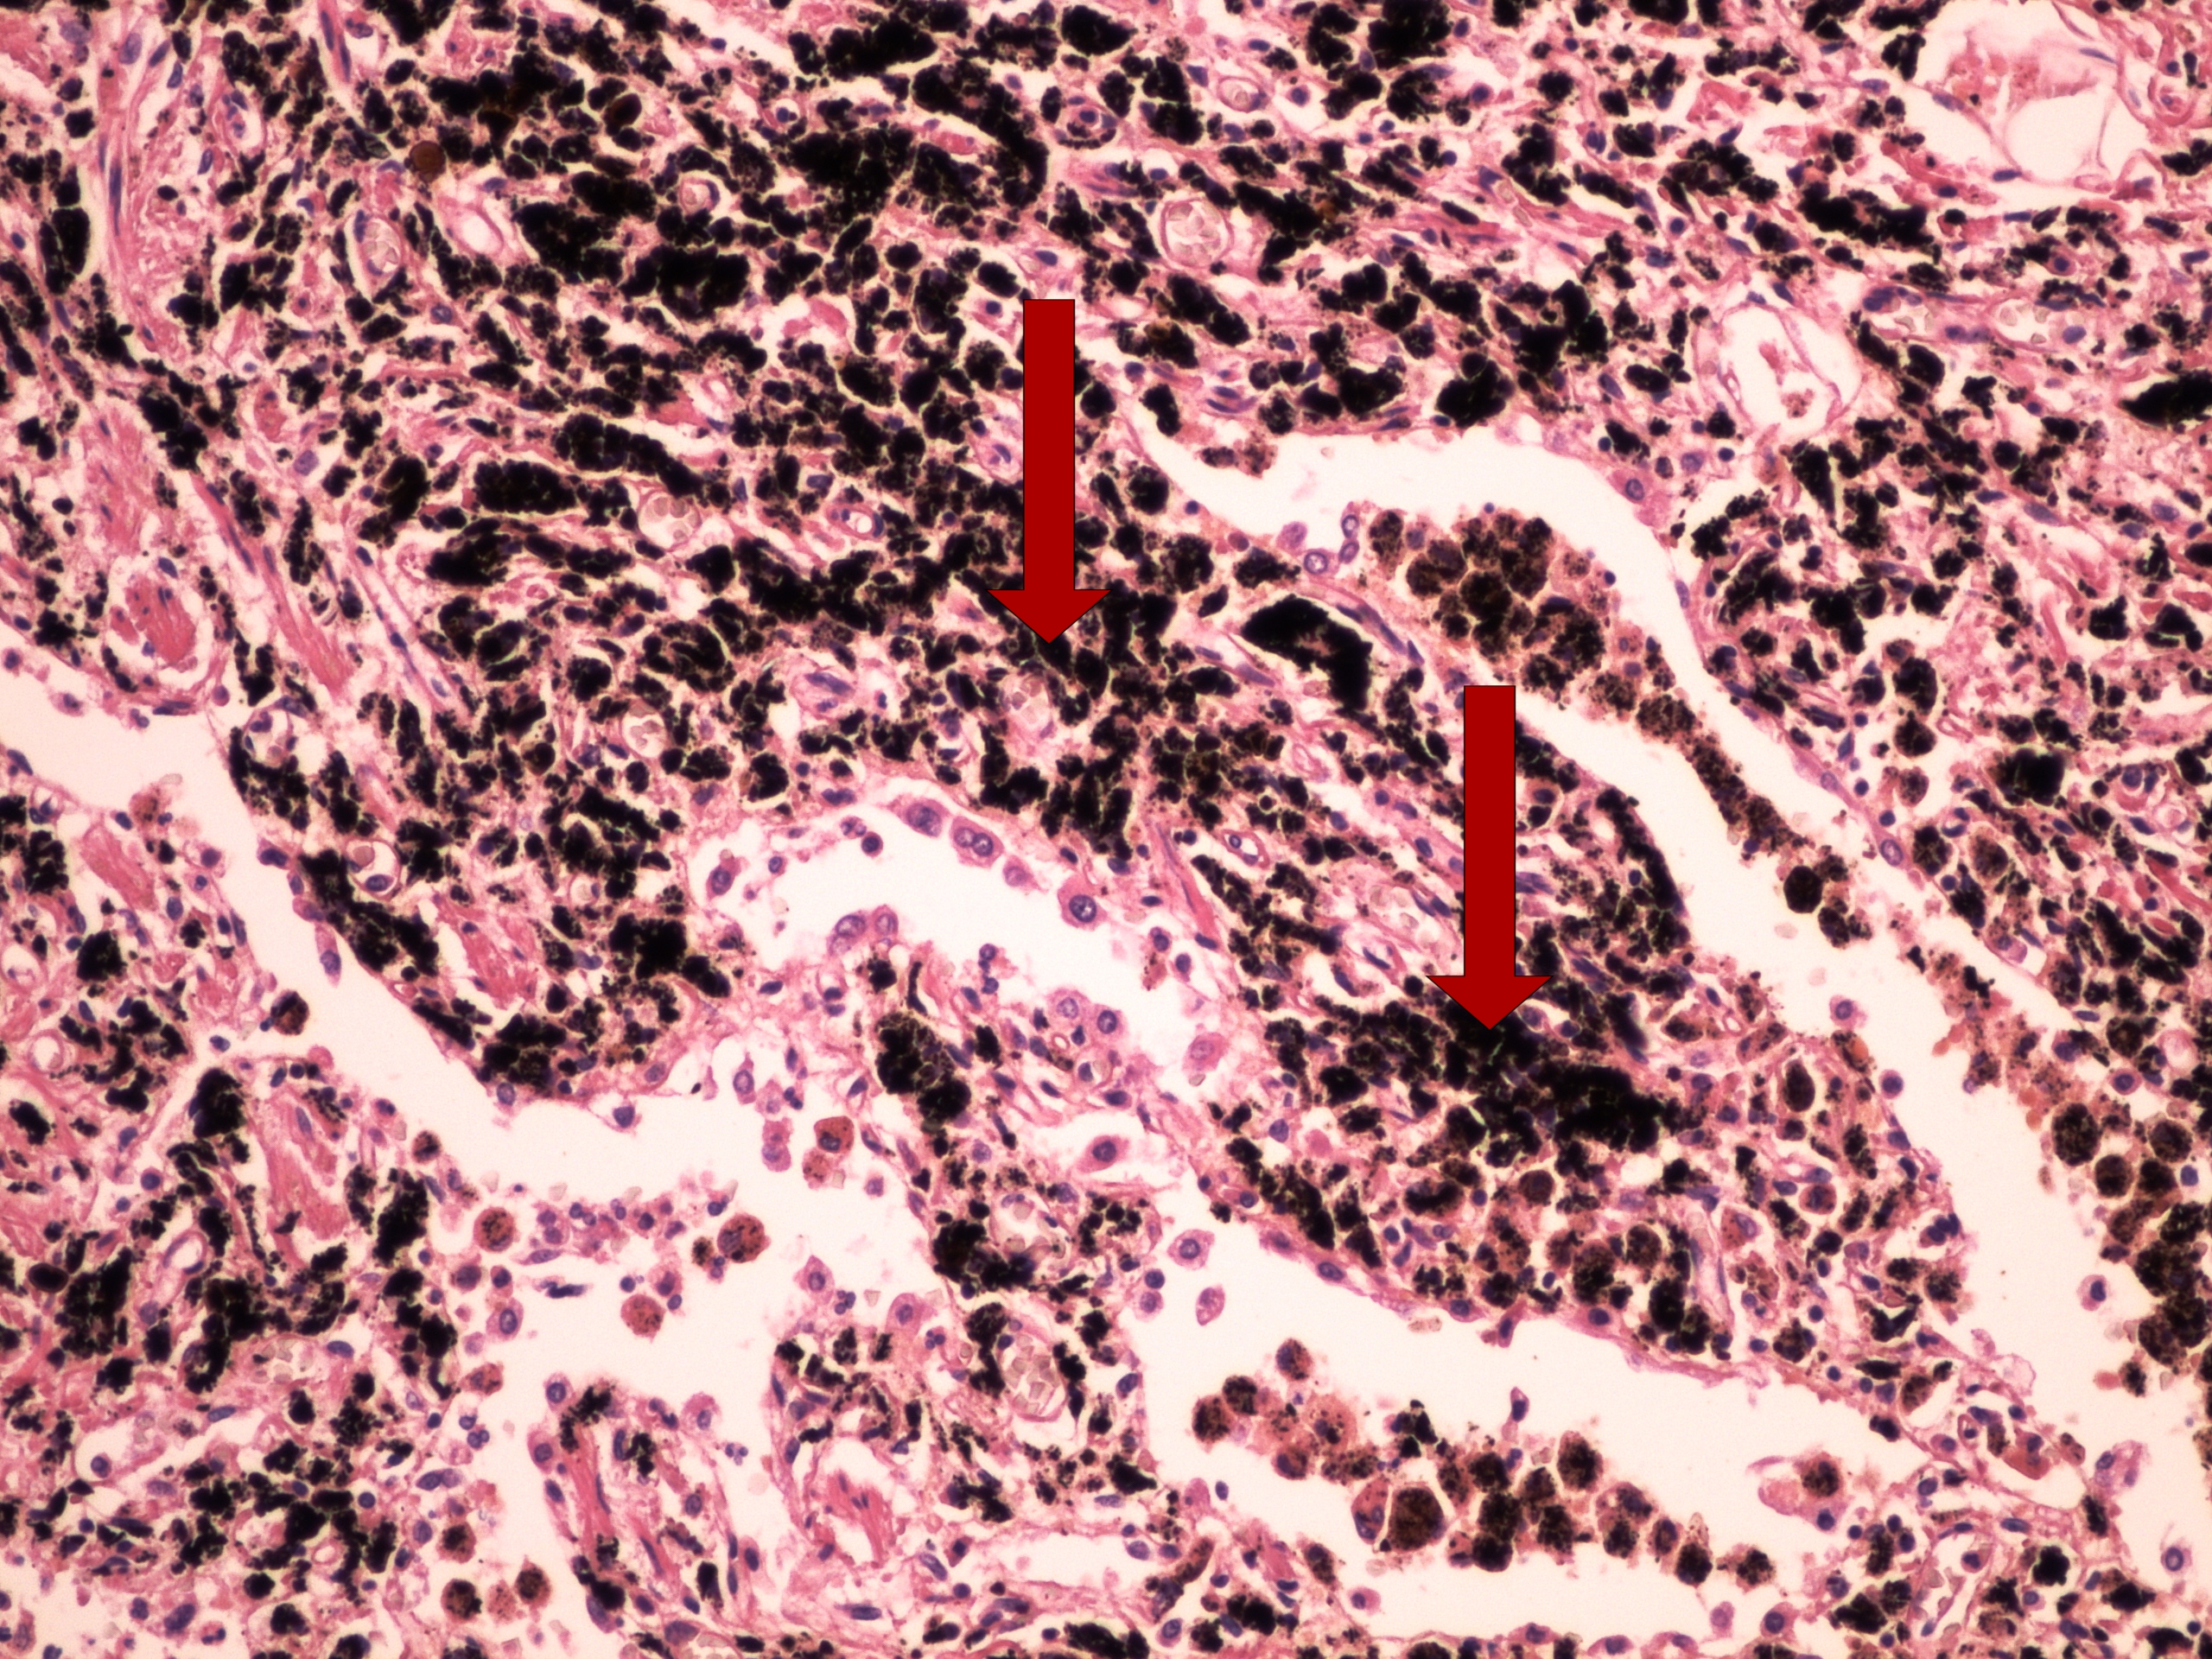

Preparát č.7 a č.8 - antrakóza

Struktury

- makrofágy

- alveoly